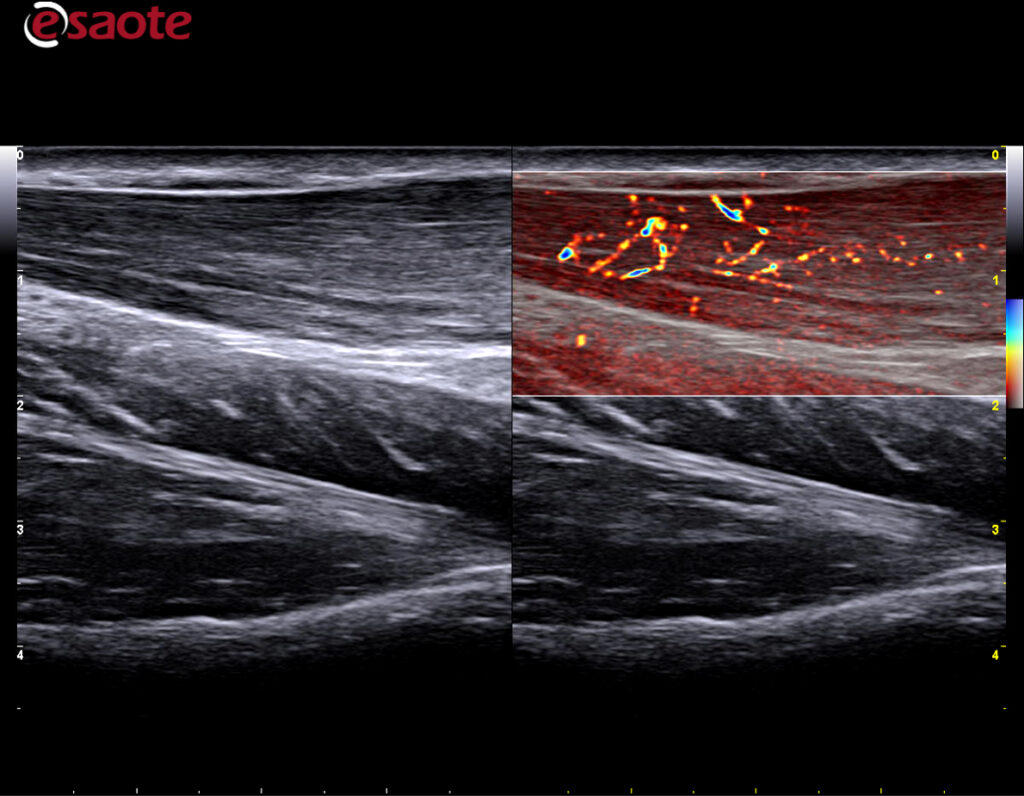

Ny doppler teknologi: MicroV.

MicroV, den nyeste dopplerteknologien fra Esaote med en enestående følsomhet selv i små kar og deteksjon av lave hastigheter. MicroV har en algoritme som helt overlegent separerer bevegelse av væske fra andre bevegelser som skaper forstyrrelser. Dette gir en helt unik dopplerfølsomhet ikke sett tidligere. Med MicroV er det mulig å endre visualiserings algoritmen for å ytterligere forsterke det du ønsker å se.

Kliniske bilder.